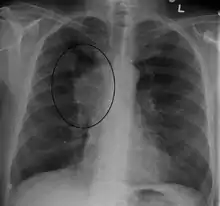

A CXR of a person with lung cancer, which was causing superior vena cava syndrome

The main techniques of diagnosing SVCS are with chest X-rays (CXR), CT scans, transbronchial needle aspiration at bronchoscopy and mediastinoscopy.[6] CXRs often provide the ability to show mediastinal widening and may show the presenting primary cause of SVCS.[6] However, 16% of people with SVC syndrome have a normal chest X-ray. CT scans should be contrast enhanced and be taken on the neck, chest, lower abdomen, and pelvis.[6] They may also show the underlying cause and the extent to which the disease has progressed.[6]